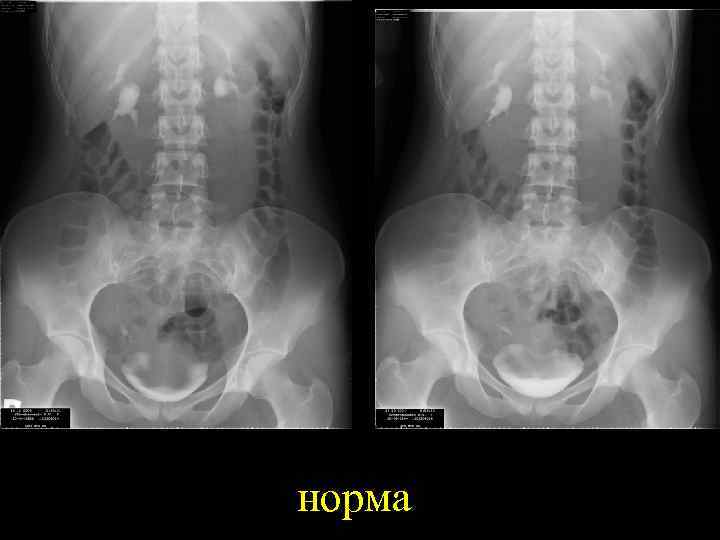

норма